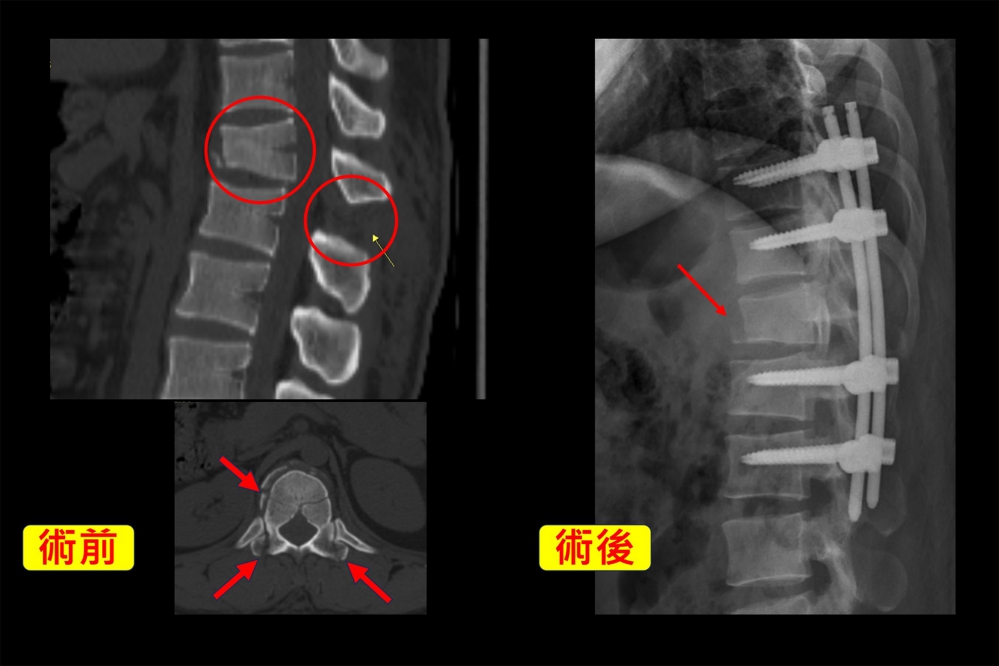

三十歲移工的華人姓氏為沈,他表示,當時身體落地後站不起來,下背非常疼痛必須有人攙扶。陳明慶醫師從X光片影像發現第十二節胸椎呈現明顯爆裂性骨折,進一步透過電腦斷層確定是脊椎骨折中嚴重的「屈曲牽張性骨折(chance fracture)」,立即為沈先生手術治療。

沈先生一個人在臺灣工作,希望儘早恢復正常生活,雇主也協助部分醫療負擔,所以選擇陳醫師建議的「經皮微創椎弓骨釘內固定」自費手術。陳明慶表示,經皮微創椎弓骨釘內固定是在沈先生骨折的第十二節胸椎,上下各兩節打入骨釘固定,即第十胸椎至第二腰椎,並撐開受傷椎體,背部有八個約一公分傷口,微創手術能減少肌肉組織破壞,術後等待時間讓骨頭自行生長修復。沈先生手術一日後就能下床走路,讓身在異鄉的他感到安心。

陳明慶醫師指出,屈曲牽張性骨折並不常見,通常是車禍或急煞車的瞬間,安全帶固定使上半身過度拉扯又屈曲,如同脊椎甩鞭條;另一個原因就是高處墜落,因重力作用,身體重摔也會過度屈曲、牽張,嚴重會導致脊椎前、中、後柱爆裂性骨折、椎體韌帶撕裂,骨骼碎片也可能傷及脊椎神經。他指出,病人下半身是否感覺麻木異常,都會影響後續手術治療方式,還好沈先生並沒有神經學方面症狀。